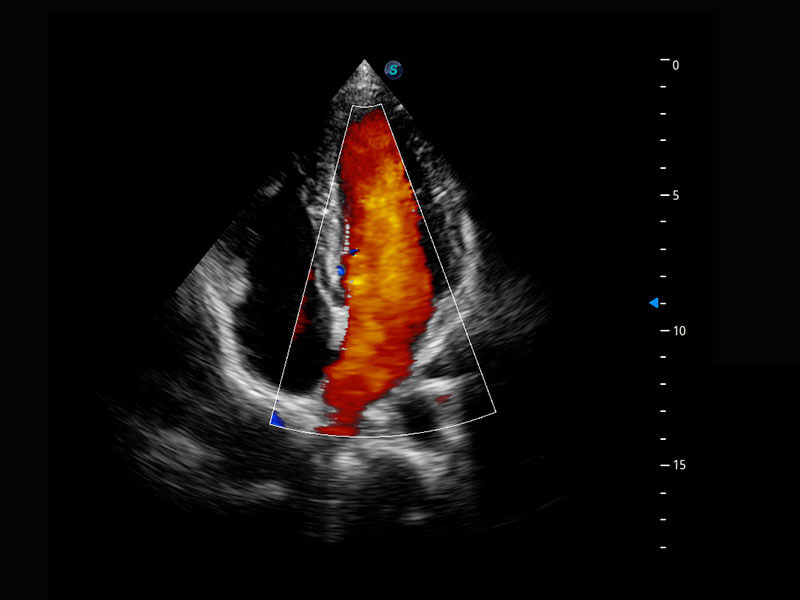

胎儿体循环

P60搭载一系列胎儿心脏成像技术,实现精细的胎儿心脏评估。

四腔心血流